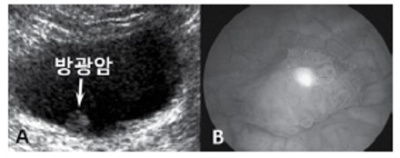

소변으로 방광이 충분히 충만한 상태에서 검사를 시행한다. 대한초음파의학회에서 권장하는 방광 초음파 검사의 표준 영상 항목은 다음과 같다. 첫째, 방광의 위쪽과 중간 부위 그리고 방광의 경부의 횡단면 영상(transverse image)을 얻는다. 둘째, 방광 중간 부위의 시상면 영상(longitudinal image)을 얻는다(Fig. 11). 방광염(cystitis)의 초음파 소견은 흔히 정상 소견이지만, 심한 경우에 방광벽이 두꺼워지고 불규칙한 점막 주름이 관찰될 수 있다. 신경인성 방광(neurogenic bladder)에서는 방광벽의 육주(trabeculation)와 방광게실(diverticulum)이 관찰되며, 방광 내압의 증가 및 방광요관 역류(vesicoureteral reflux)로 인해 수신증과 요관의 확장이 동반될 수 있다. 방광의 악성종양 대부분은 요로상피암이며 방광 내강으로 돌출된 종괴의 형태가 가장 흔하다(Fig. 12). 또한, 동시기 암(synchronous cancer)이 방광의 다른 부위, 요관 및 신우 등에서 동반될 수 있으므로 방광암이 의심될 때에는 전반적인 요로계의 관찰이 필요하다.

신장 및 방광 12.jpg

Fig. 12. 방광암의 초음파(A)와 방광경 소견(B)